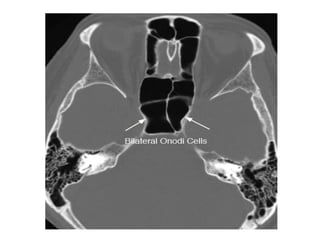

Onodi Cells

• posterior ethmoidal cells extending supero

lateral to the sphenoid sinus & can either

abut to or impinging upon the optic nerve.

• When these Onodi cells abut or surround

the optic nerve, the nerve is at risk when

surgical excision of these cells is

performed.

• It is also a potential cause of incomplete

sphenoidectomy.

Onodi Cells • posteriorethmoidal cells extending supero lateral to the sphenoid sinus & can either abut to or impinging upon the optic nerve. • When these Onodi cells abut or surround the optic nerve, the nerve is at risk when surgical excision of these cells is performed. • It is also a potential cause of incomplete sphenoidectomy.